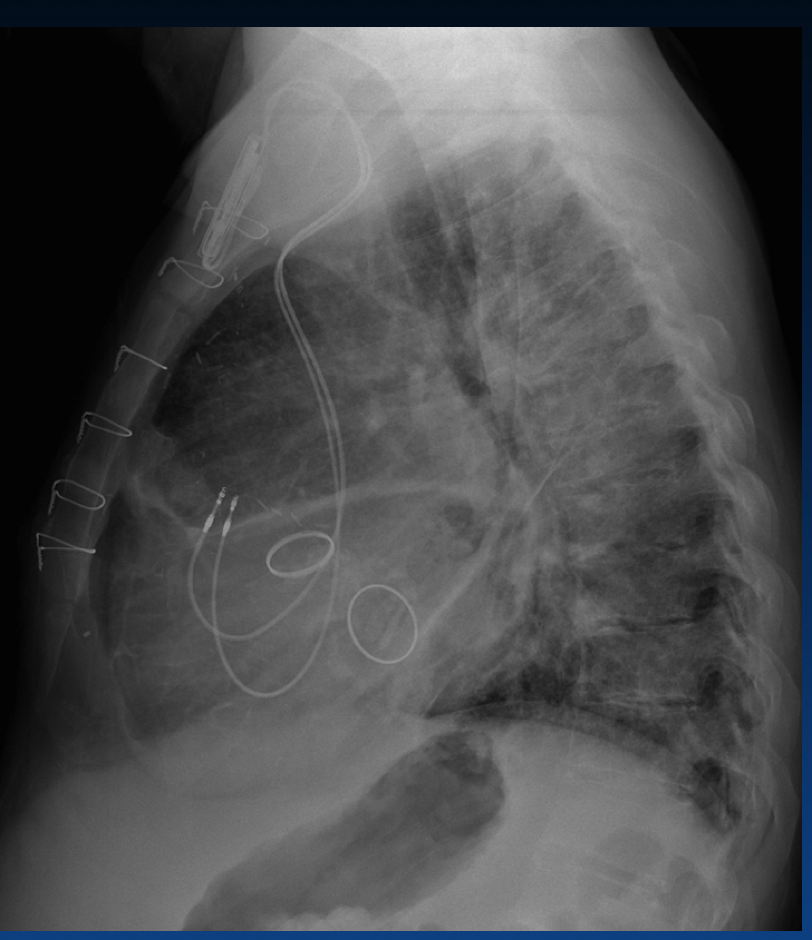

What is Twiddler Syndrome?

Name the Pacemaker/ICD Complication